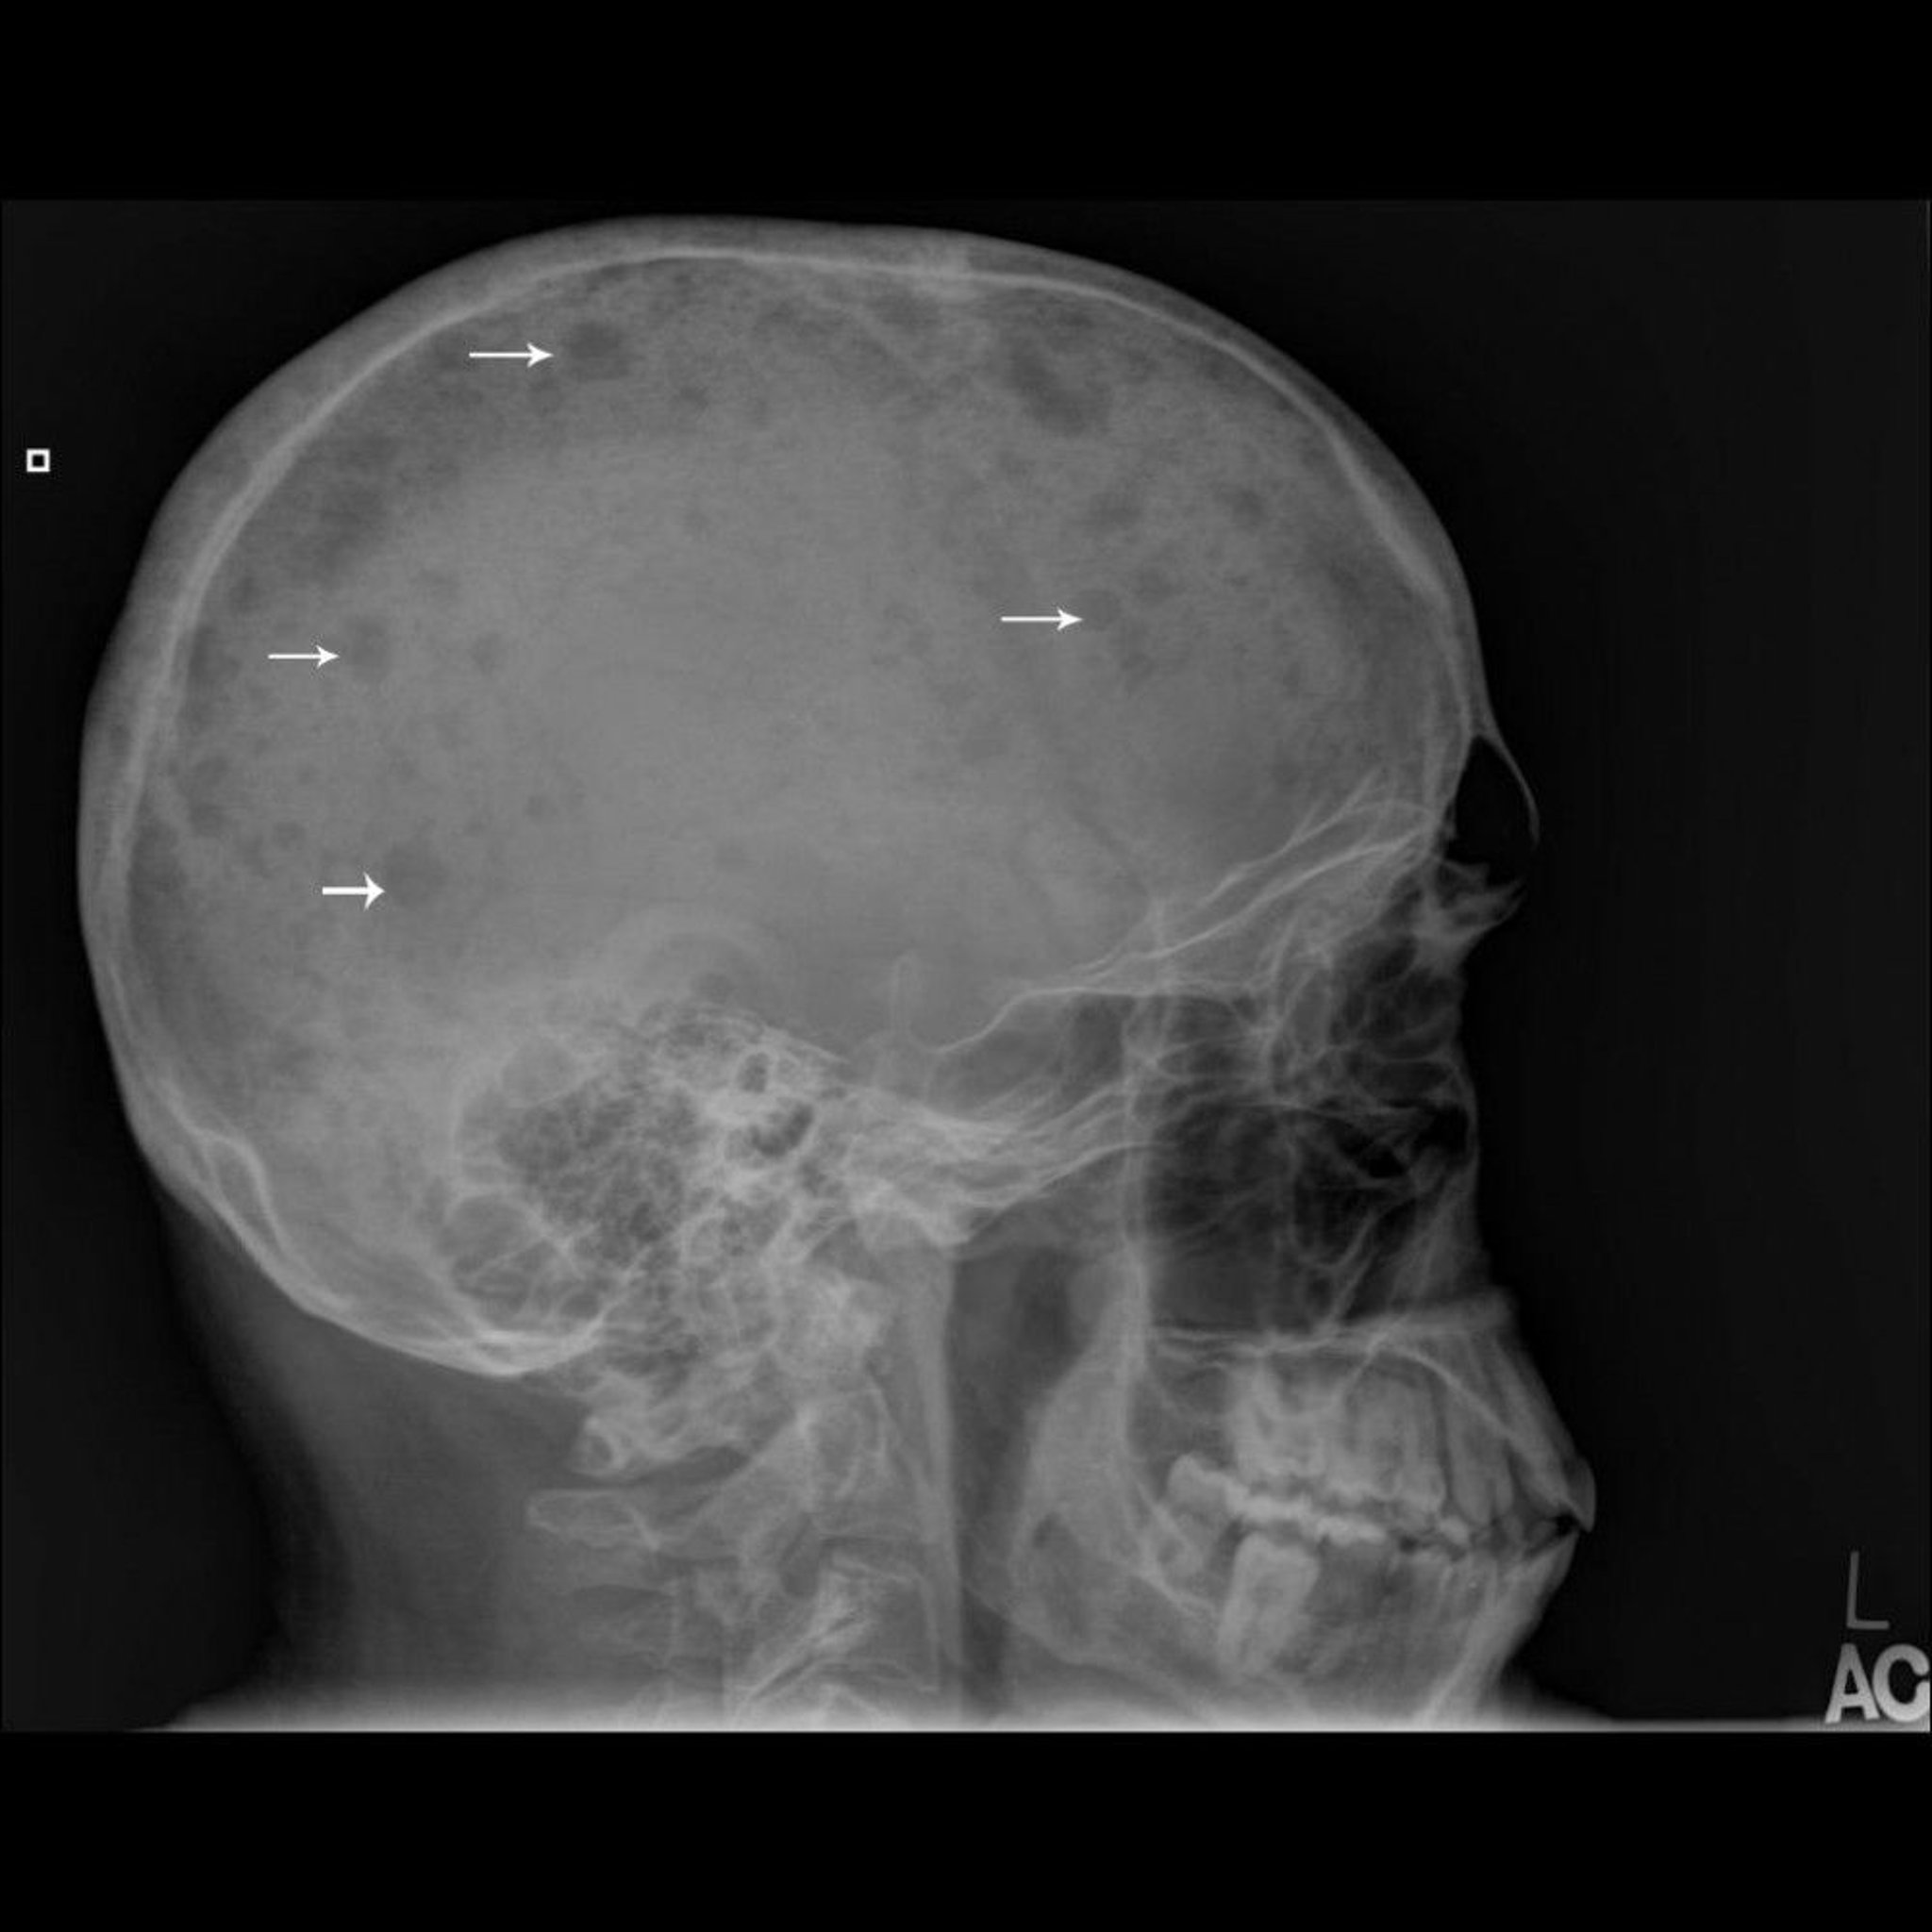

This skull radiograph shows multiple, punched-out lesions in the bone (arrows), which are typical of multiple myeloma.

Image courtesy of Michael J. Joyce, MD, and Hakan Ilaslan, MD.